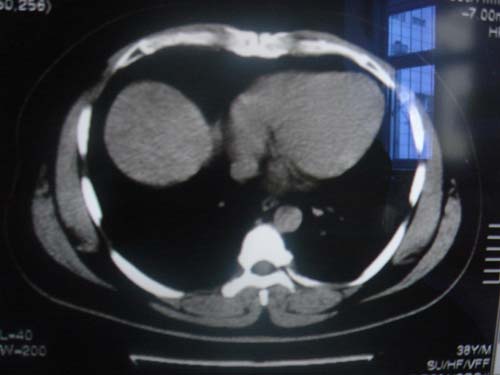

患者 男 40 右上腹不适 有胆囊息肉病史2年

本例就是胆囊比较大,内密度不很均匀,疑有砂砾状结石,未见息肉以及其他异常。

肝脏增大,

最后二副图像示胆囊壁增厚,与肝分界欠清,建议强化ct或磁共振

片中示肝脏的ct值低于脾脏,肝脏右叶外缘部份凹凸不平,考虑脂肪肝,肝硬化可能。结合其检查如b超或ct增强检查。

胆囊未见明显异常,肝脏密度似比脾脏密度低,测量一下ct值排除一下脂肪肝.当然做一下增强或mr就更好了.

肝右叶密度不均,脾大。强烈要求增强扫描除外浸润型肝癌。

肝大   密度降低  脾大  脂肪肝?